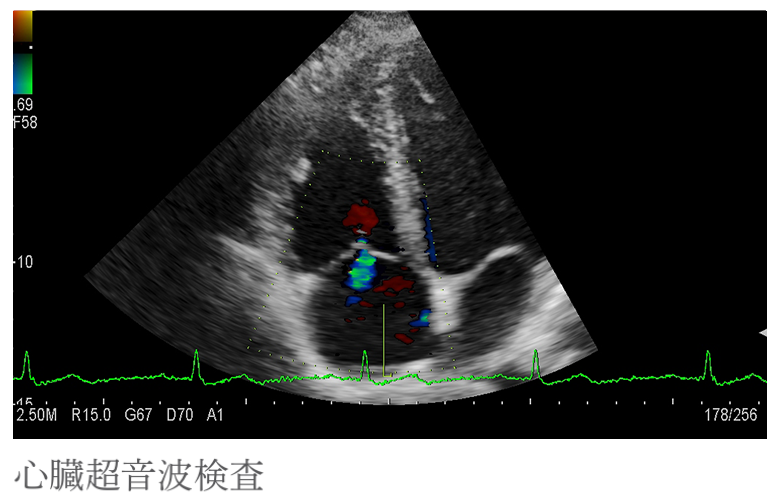

・心臓超音波検査

心臓が動いている様子を映し出して、壁の動きや弁の状態などを検査します。